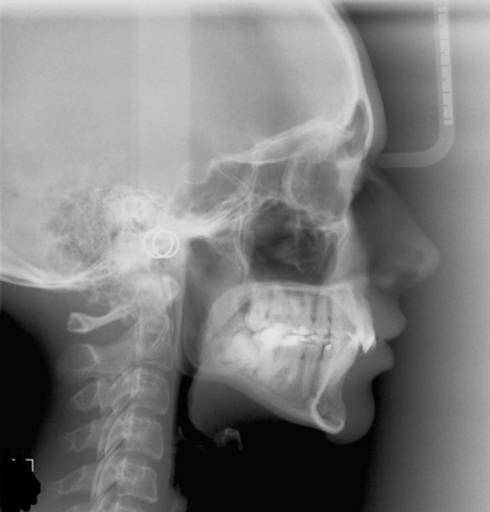

My lower jaw is not right

I'm a 15 year old. I hav my lower jaw exceeding upper jaw. Can you tell me about the cost and methods of the surgery ? I went to a dentist and he says I had to remove my tree teeth which scared me to hell. I never decided to do the surgery. But. Will my lower jaw keep on exceeding ? Im really worried ! Will it keep on increasing ?